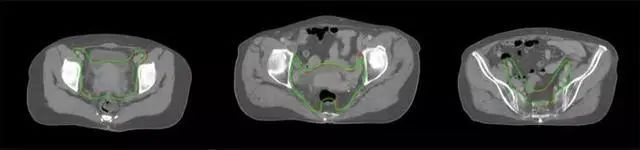

四、放射治療智能勾畫(huà)軟件

放射治療,簡(jiǎn)稱放療,是治療腫瘤主要手段之一,利用放射線破壞照射區(qū)(靶區(qū))的細(xì)胞,使腫瘤細(xì)胞停止分裂直至死亡,醫(yī)生通常把放射治療形象的比喻為“打靶”,放療前精準(zhǔn)勾畫(huà)腫瘤靶區(qū)范圍是腫瘤放射治療的關(guān)鍵步驟。傳統(tǒng)的靶區(qū)勾畫(huà)醫(yī)生會(huì)根據(jù)患者多張CT、MRI影像片憑借經(jīng)驗(yàn)進(jìn)行,比較耗時(shí),治療的病人數(shù)量也有限,且靶區(qū)勾畫(huà)缺少行業(yè)統(tǒng)一的規(guī)范和標(biāo)準(zhǔn),無(wú)法達(dá)到同質(zhì)化,勾畫(huà)精確度不理想。

技術(shù)原理

基于深度學(xué)習(xí)人工智能的放療靶區(qū)智能勾畫(huà)技術(shù)和自動(dòng)計(jì)劃技術(shù),基于全面的市場(chǎng)調(diào)研和臨床專業(yè)意見(jiàn),采用獨(dú)創(chuàng)的基于小樣本量的人工智能算法,實(shí)現(xiàn)放療靶區(qū)和危及器官的快速全自動(dòng)勾畫(huà)。

產(chǎn)品優(yōu)勢(shì)

縮短至幾分鐘內(nèi)便可完成,大幅提升了放療效率,且人工智能平臺(tái)完成的靶區(qū)勾畫(huà)可基本滿足臨床醫(yī)生需求,專家只需審核時(shí)細(xì)微調(diào)整,可顯著提高靶區(qū)勾畫(huà)的規(guī)范化及精準(zhǔn)度,讓放療智能化,標(biāo)準(zhǔn)化??筛采w食管癌、鼻咽癌、直腸癌、宮頸癌、肺癌等多種病種。